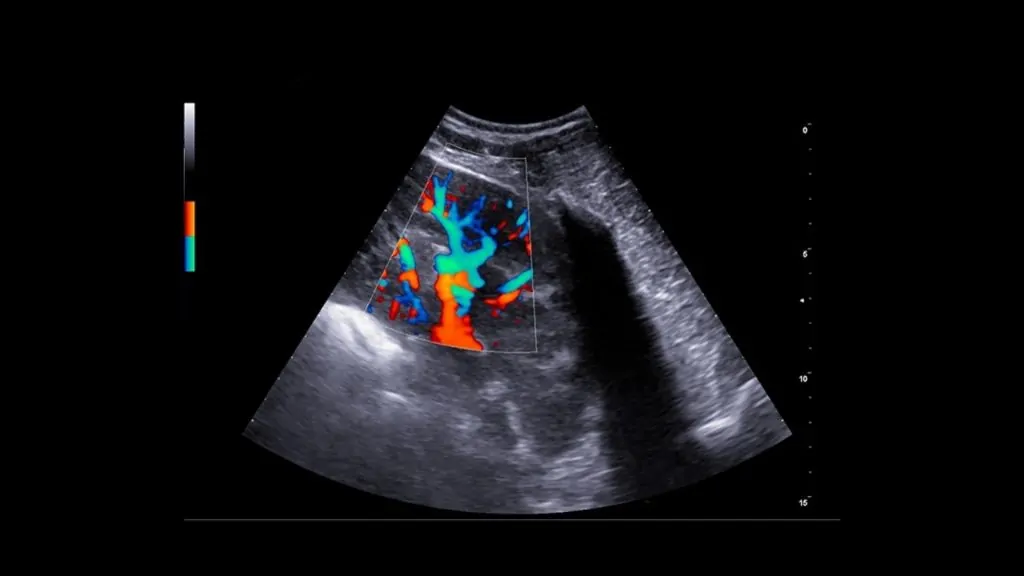

Karaciğer parankimi, portal/hepatik damarlar, safra kesesi ve biliyer sistem değerlendirilir.

Gerekli durumlarda Doppler ile vasküler yapıların analizi yapılabilir; portosistemik şant şüphesinde yönlendirici olabilir.

• Gerekli görülen durumlarda Doppler USG ile kan akımı analizi yapılabilir.